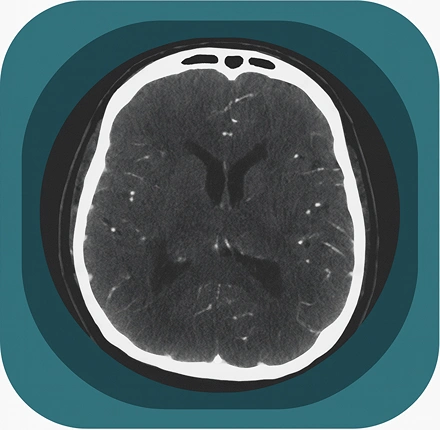

Explore full-body CT anatomy in 3 planes. Our high-resolution, carefully labelled images reveal micro-anatomy—ideal for radiologists, radiographers and surgeons.